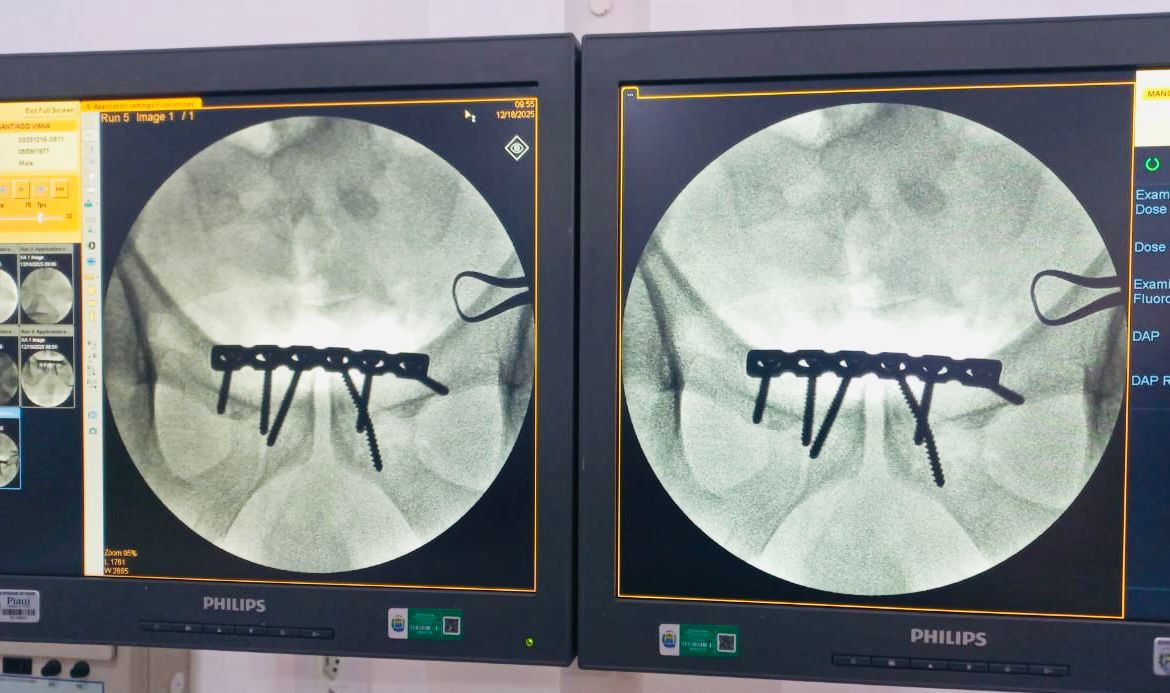

Hospital de Piripiri realiza, pela primeira vez, cirurgia ortopédica de alta complexidade em paciente com fratura de bacia

O Hospital Regional Chagas Rodrigues (HRCR), em Piripiri, realizou, pela primeira vez, o tratamento cirúrgico de fratura do anel pélvico — popularmente conhecida como fratura da bacia, representando um marco histórico para a unidade e um avanço importante na ampliação dos serviços ortopédicos oferecidos à população.

A fratura pélvica ocorre nos ossos do quadril, sacro e cóccix, que juntos formam o anel pélvico. Em casos mais graves, como quando há ruptura do anel, a fratura envolve pelo menos dois pontos ósseos, resultando em maior instabilidade e complexidade no tratamento.

O procedimento foi conduzido por uma equipe multiprofissional especializada, evidenciando a capacidade técnica do hospital para atender casos de média e alta complexidade, com segurança, eficiência e qualidade assistencial. A cirurgia foi realizada pelo cirurgião Gutemberg Soares, com auxílio do Dr. Felipe Verner, tendo como anestesista Erick Zenteno, além do suporte essencial da equipe de enfermagem.

O paciente, do sexo masculino, foi vítima de trauma automobilístico, apresentando fratura do anel pélvico do tipo “livro aberto”, considerada um trauma grave. Até então, casos como esse exigiam a transferência para unidades de referência em Teresina. Nesta ocasião, todo o tratamento cirúrgico foi realizado no próprio HRCR, com suporte completo de anestesia, enfermagem, materiais adequados e segurança assistencial.

Para o diretor-geral do HRCR, Edilto Franco, a realização do procedimento simboliza um avanço significativo para a saúde regional. “Estamos vivendo um momento de evolução no hospital. Conseguimos realizar uma cirurgia de alta complexidade que antes exigia transferência para a capital, garantindo mais agilidade, segurança e cuidado humanizado ao paciente”, destacou o gestor.

O cirurgião Gutemberg Soares também ressaltou a importância do avanço técnico da unidade. “Esse procedimento demonstra a evolução da linha do trauma ortopédico no HRCR. Hoje contamos com equipe capacitada, estrutura adequada e todo o suporte necessário para oferecer um tratamento resolutivo, seguro e cada vez mais humanizado”, afirmou o médico.

A realização da cirurgia reforça o compromisso do Hospital Regional Chagas Rodrigues com a regionalização da saúde, sob gestão do Instituto Saúde e Cidadania (Isac), com apoio da Secretaria da Saúde do Piauí (Sesapi), permitindo que o paciente fosse tratado na própria unidade, sem a necessidade de deslocamento até Teresina, garantindo mais conforto, agilidade e proximidade com a família.